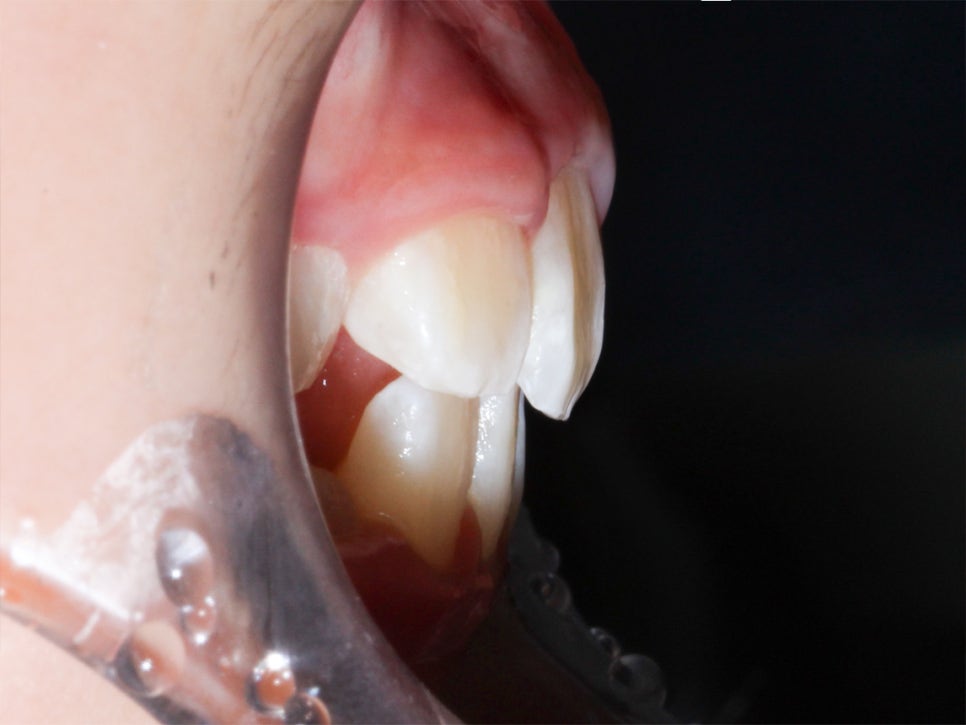

환자분의 상태를 살펴보면

치아가 날 공간이 부족하거나 치아가 나오는 방향에서

앞니가 앞으로 나오고 다른 치아가 기울어지면서

거꾸로 물리는 현상이 발생한 걸로 보여요.